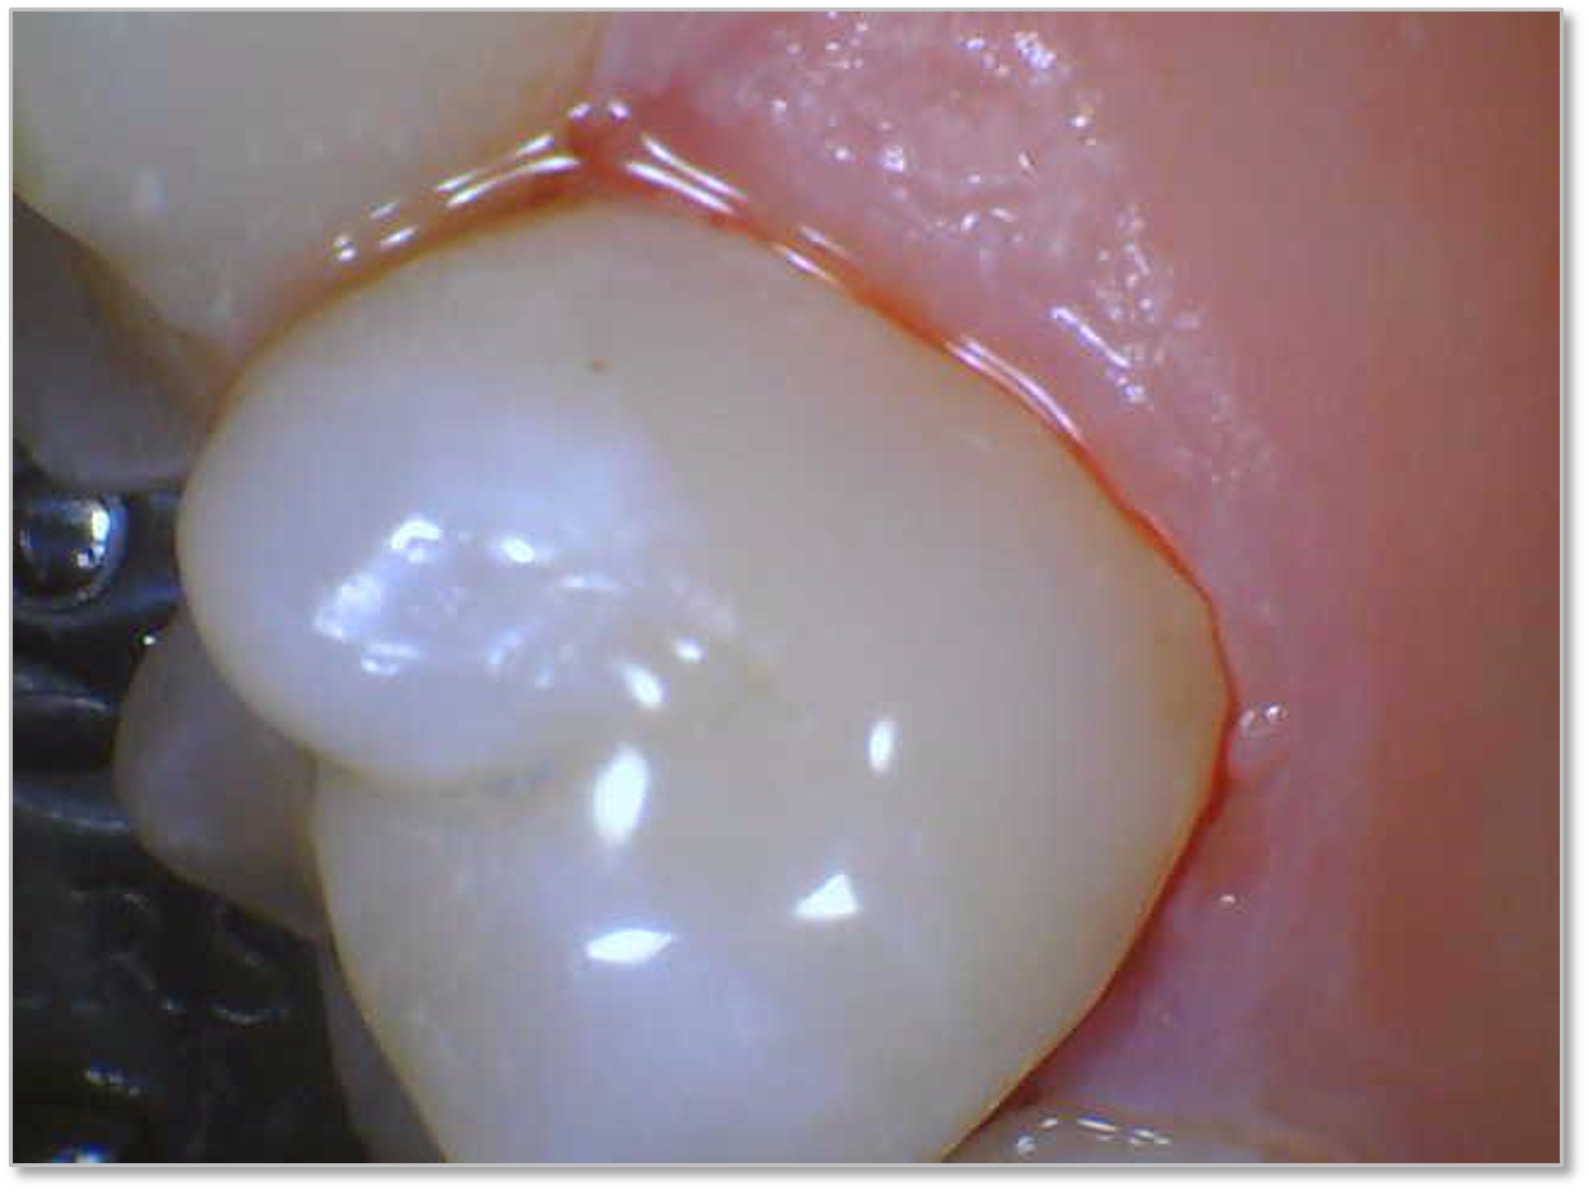

Figure 6a through Figure 6d show a procedure using a bulk fill packable as an interproximal Class 2, without using a bulk fill flow and not done with the snowplow technique to see how well the composite adapted to the margin. A light curable resin-modified calcium silicate liner (Bisco TheraCal LC) was used to perform an indirect pulp cap. A packable bulk fill composite was applied as a single increment layer to successfully restore the tooth. The material (Kerr SimpliShade Bulk Fill Packable) provided good adaptation to the tooth without gaps or polymerization stress lines and demonstrated great polishability and blendability. The patient reported no post operative sensitivity or discomfort in the 9 months after the restoration was performed. Sensitivity can be a concern if a composite is subjected to too much polymerization shrinkage.

Fig 6d. A procedure using a bulk fill packable as an interproximal Class 2, without using a bulk fill flow and not done with the

snowplow technique. A light curable resin-modified calcium silicate liner (Bisco TheraCal LC) was used to perform an indirect pulp cap. A

packable bulk fill composite was applied as a single increment layer. The material (Kerr SimpliShade Bulk Fill Packable) was used to provide

good adaptation to the tooth without gaps or polymerization stress lines and demonstrated great polishability and blendability.

Fig 6d.